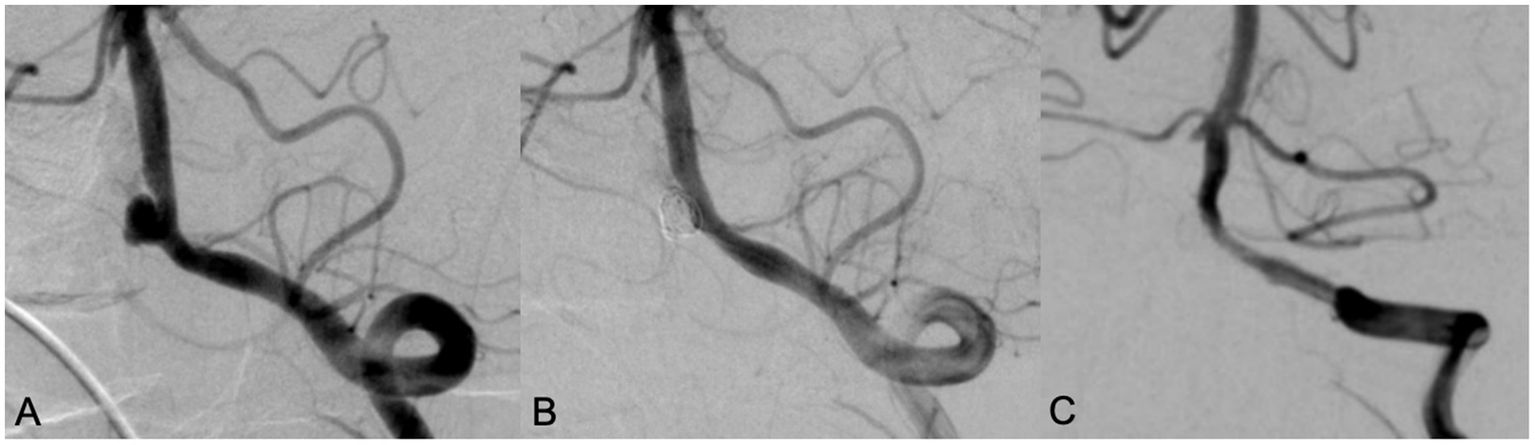

All patients successfully completed SAC for WNIA, and the technical success rate was 100%. Immediate postembolization angiography showed that in the Neuroform Atlas group, 22 aneurysms (81.5%, 22/27) achieved MRRC Class I, 5 aneurysms (18.5%, 5/27) achieved Class II, and 0 aneurysms (0%) achieved Class III. In the LVIS group, 25 aneurysms (73.5%, 25/34) achieved MRRC Class I, 9 aneurysms (26.5%, 9/34) achieved Class II, and 0 aneurysms (0%) achieved Class III. There was no significant difference in the initial obliteration class between the two groups (p = 0.549) (Table 2). Representative cases of the Atlas group and LVIS group were shown in Figures 1, 2, respectively.

Figure 1. A 78 year old female with intermittent headache and left lower limb weakness for 9 days was admitted, DSA examination showed an anterior communicating artery aneurysm with a wide neck (A). Neuroform Atlas stent assisted coiling embolization was performed. Immediate angiography after embolization showed the aneurysm was almost occluded with MRRC grade 2 (B). Angiography performed in 12 months’ follow-up showed that the aneurysm was occluded well with MRRC grade 1 (C).